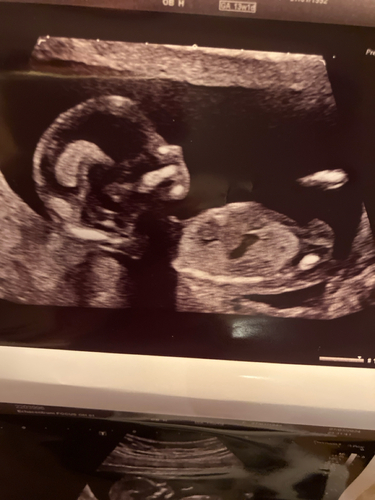

Is het op deze echo's te zien? Hier was ik 13+5

Alleen linksboven, maar wel duidelijk 💙🤭